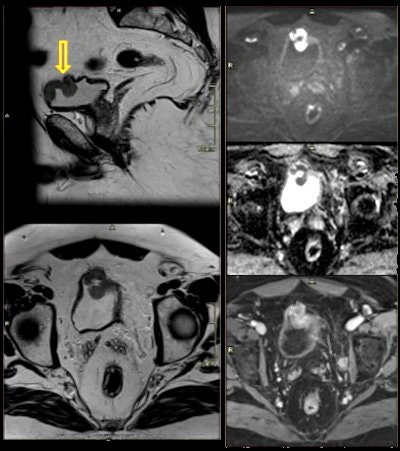

67-year-old man with vesicle cancer. High prostate-specific antigen (PSA) level and hematuria. Incidental finding: polypoid lesion on anterior wall of bladder with restricted diffusion and contrast enhancement.- Hydrocele: acquired or congenital serous fluid collections between the layers of the tunica vaginalis surrounding a testis or spermatic cord